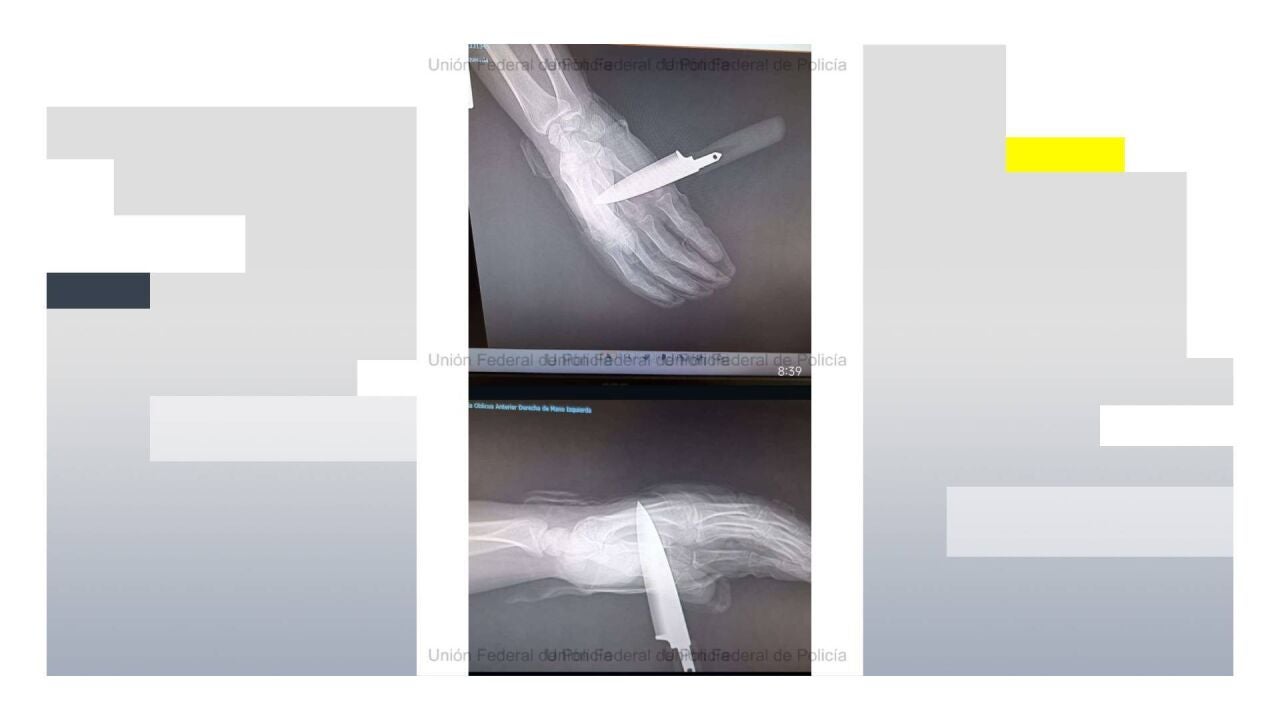

Radiografía de la mano del agente de la Policía Nacional apuñalado en Baza (Granada)UNIÓN FEDERAL DE POLICÍA (UFP)

El agresor no se quedó atrás y, en lugar de frenar los ataques, trató de asestar una segunda puñalada. Aunque el agente logró repeler el golpe parcialmente, el arma blanca llegó a atravesarle la mano, provocándole una herida de consideración.

Por su parte, el agente herido tuvo que ser trasladado a un centro hospitalario con el cuchillo aún clavado en la mano.